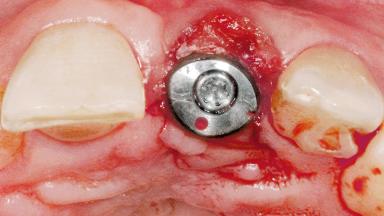

Type of Implants One-Piece

Attachment One-Piece

Placement Protocol Early or late implant placement

Bone Volume Deficient horizontally, requiring prior grafting